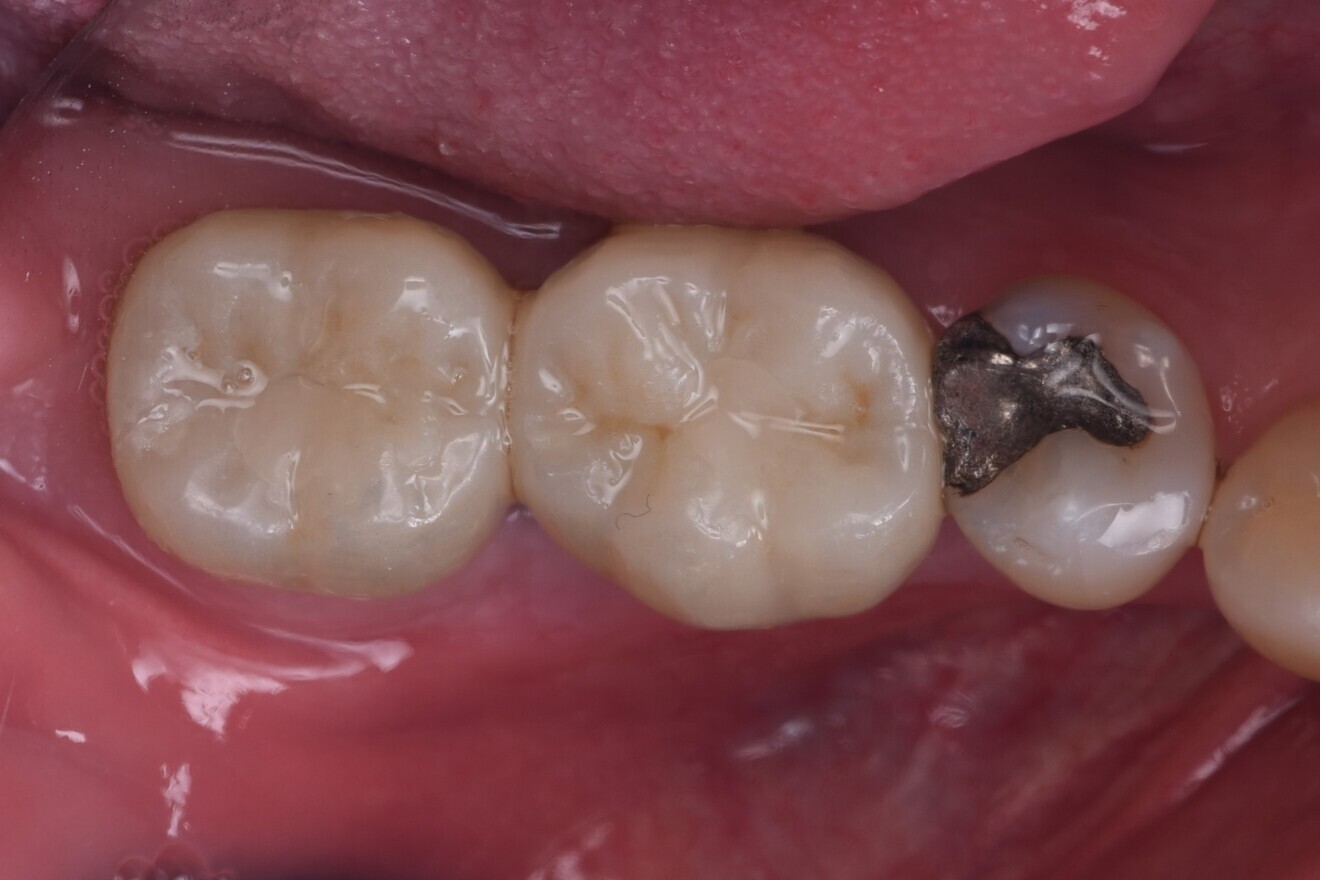

The immediate placement of the CONELOG PROGRESSIVE-LINE implants in both molar sockets proceeded smoothly, achieving excellent primary stability. The hard and soft tissue was well maintained, and excellent soft-tissue thickness and a stable band of keratinised tissue were achieved (Figs. 13–16). This approach not only preserved the existing bone and soft tissue but also provided a solid foundation for future prosthetic restoration. This case highlights the importance of case selection and choice of implant and grafting material in optimising long-term outcomes in implant dentistry.

Immediate placement, when feasible, offers significant advantages in simplifying long-term maintenance compared with extensive hard- and soft-tissue reconstruction. The CONELOG PROGRESSIVE-LINE implant system continues to be a reliable choice for immediate placement, particularly in molar sites, owing to its excellent design and adaptability, and the CONELOG guided kit’s screw-in carriers allow for very accurate positioning.